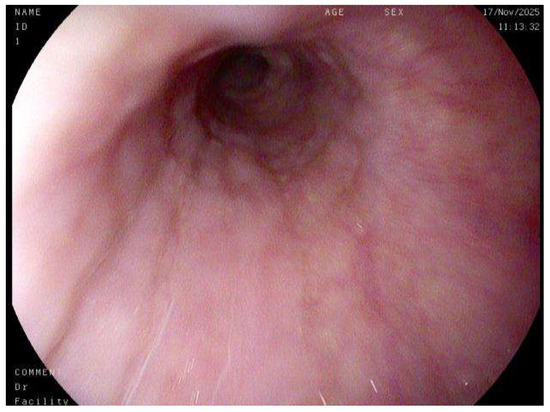

Special considerations are required for the evaluation of gastrointestinal pathology in the pediatric population. The spectrum of pediatric gastrointestinal tract disorders is broad, and the diagnosis often requires a different approach from that in adults. In addition, certain conditions (e.g., congenital enteropathies, monogenic inflammatory bowel disease) are rarely encountered, even at large pediatric centers. Thus, these specimens pose unique diagnostic challenges for many practicing pathologists. The aim of this Special Issue is to highlight recent advances in the field of pediatric gastrointestinal pathology. This Special Issue will also provide a practical overview of relevant disorders for pathologists and clinicians who diagnose and manage pediatric patients. Various types of articles (e.g., case series, original research, reviews) on common and rare entities are welcome.